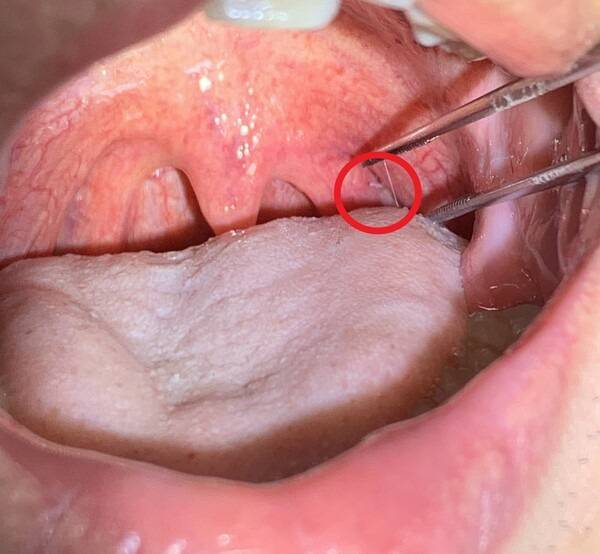

가시가 걸렸다고 느껴지면 우선 침을 삼키는 행동부터 멈추셔야 합니다. 거울을 보고 입안을 살짝 벌려 가시가 보이는 위치라면 깨끗한 핀셋으로 조심스럽게 제거할 수 있습니다. 이때 손과 도구는 반드시 깨끗해야 합니다. 가시가 보이지 않거나 깊숙한 느낌이 든다면 억지로 빼려고 하지 마세요. 물을 소량만 천천히 마셔보는 정도까지만 시도하셔야 합니다. 통증이 계속된다면 바로 병원에 가는 것이 가장 안전합니다.

가시가 걸린 뒤 통증이 점점 심해지거나, 침을 삼키기 힘들고 피 맛이 느껴진다면 이미 점막 손상이 시작됐을 가능성이 큽니다. 또 하루 이상 이물감이 계속된다면 가시가 그대로 남아 있을 확률이 높습니다. 아이나 노약자의 경우에는 증상을 정확히 표현하지 못하기 때문에 더 주의가 필요합니다. 병원에서는 내시경이나 전문 도구로 빠르고 안전하게 제거할 수 있으니, 괜히 버티지 마시고 도움을 받으셔야 합니다.